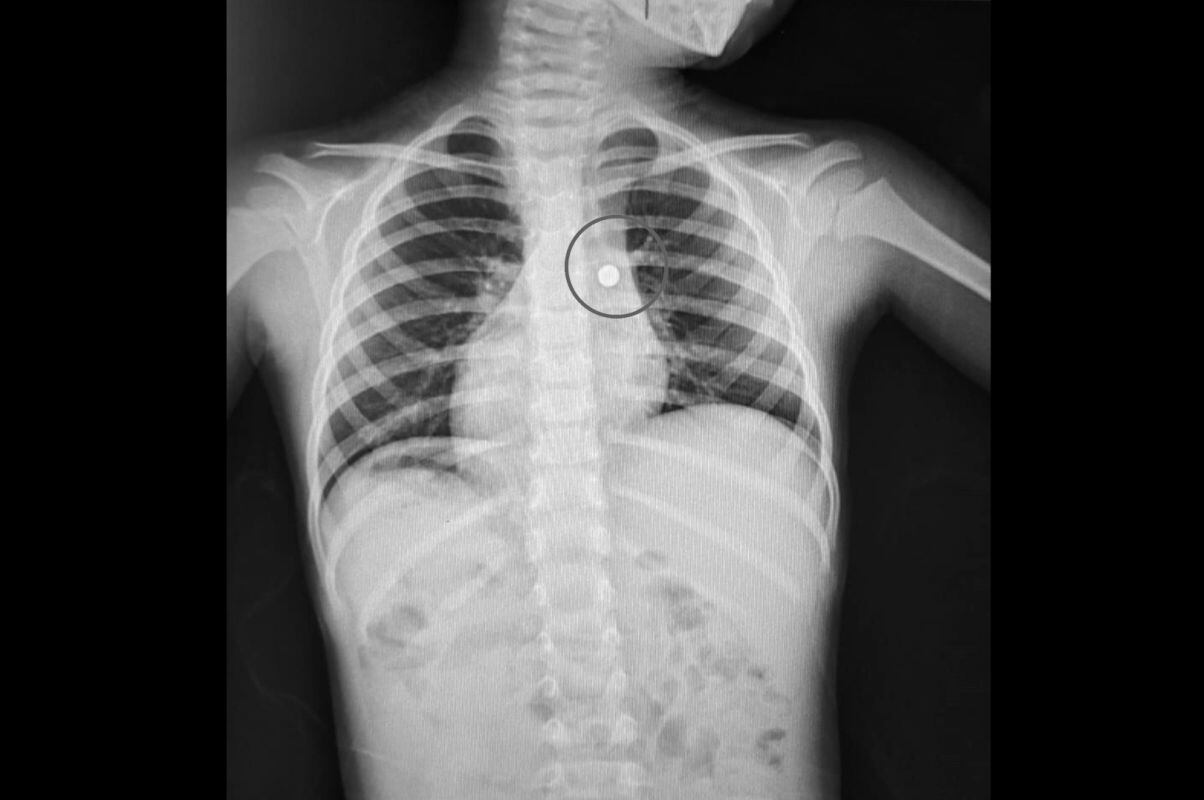

Médicos especialistas de la Red Social de Essalud La Libertad salvaron la vida de un niño de 4 años que tenía una pila alojada en un pulmón tras acudir de emergencia ya que no podía respirar.

Los médicos neumólogos del hospital Lazarte le practicaron diversos exámenes y determinaron que que el menor tenía, en el bronquio del pulmón derecho, una pila de reloj de 8mm.

El doctor Julio Córdova Pacherre, médico neumólogo del nosocomio en La Libertad, explicó que el menor ingirió por la boca este cuerpo metálico y que pasó por la vía aérea, alojándose en el bronquio.

Al paciente se le practicó una broncoscopia. “Se utilizó un broncoscopio portátil que cuenta con fibras del tamaño adecuado para la edad del menor. La intervención fue realizada de emergencia y participó personal de neumología altamente capacitado en broncoscopia básica y avanzada”, comentó el galeno.

Por último, el especialista comentó que el paciente fue dado de alta y deberá continuar con algunos controles médicos en su centro asistencial de origen.